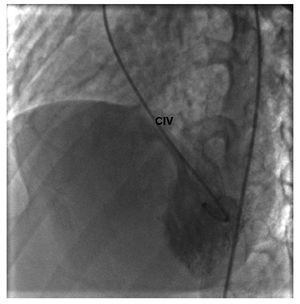

Figura 4 Angiocardiograma en posición oblicua izquierda. Se observa el paso de medio de contraste del ventrículo izquierdo al derecho por la comunicación interventricular. La arteria coronaria derecha insinúa la dilatación del ventrículo derecho. CIV: comunicación interventricular.